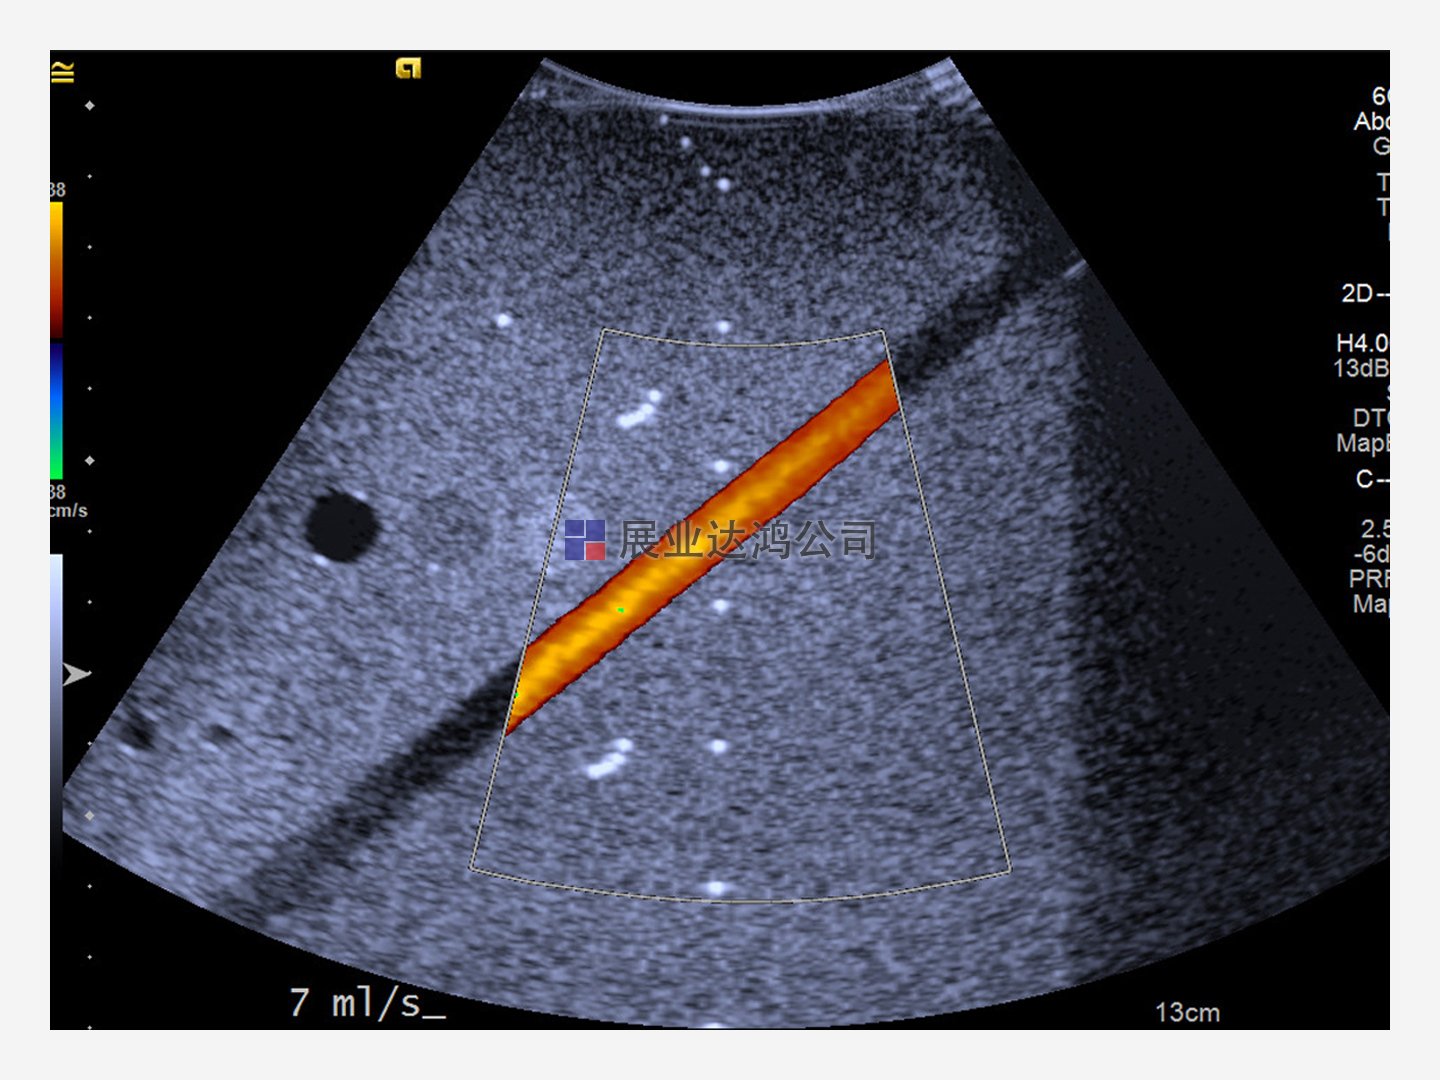

驗證超聲系統(tǒng)和換能器的性能。Doppler 403和 Mini-Doppler 1430流動體模使用精確的流速和專有的血液模擬流體幫助評估系統(tǒng)速度。

確定各種角度和光束方向的最大信號穿透、通道隔離和流速讀數(shù)精度——其能力超過 ACR、ECR、AIUM 和其他 QA 程序要求。水平段模擬頸動脈,對角段用于測量多普勒靈敏度和開發(fā)掃描技術(shù)。

提供恒定、脈動和自定義流量模式選項。體積流量設(shè)置支持可靠的系統(tǒng)速度測試